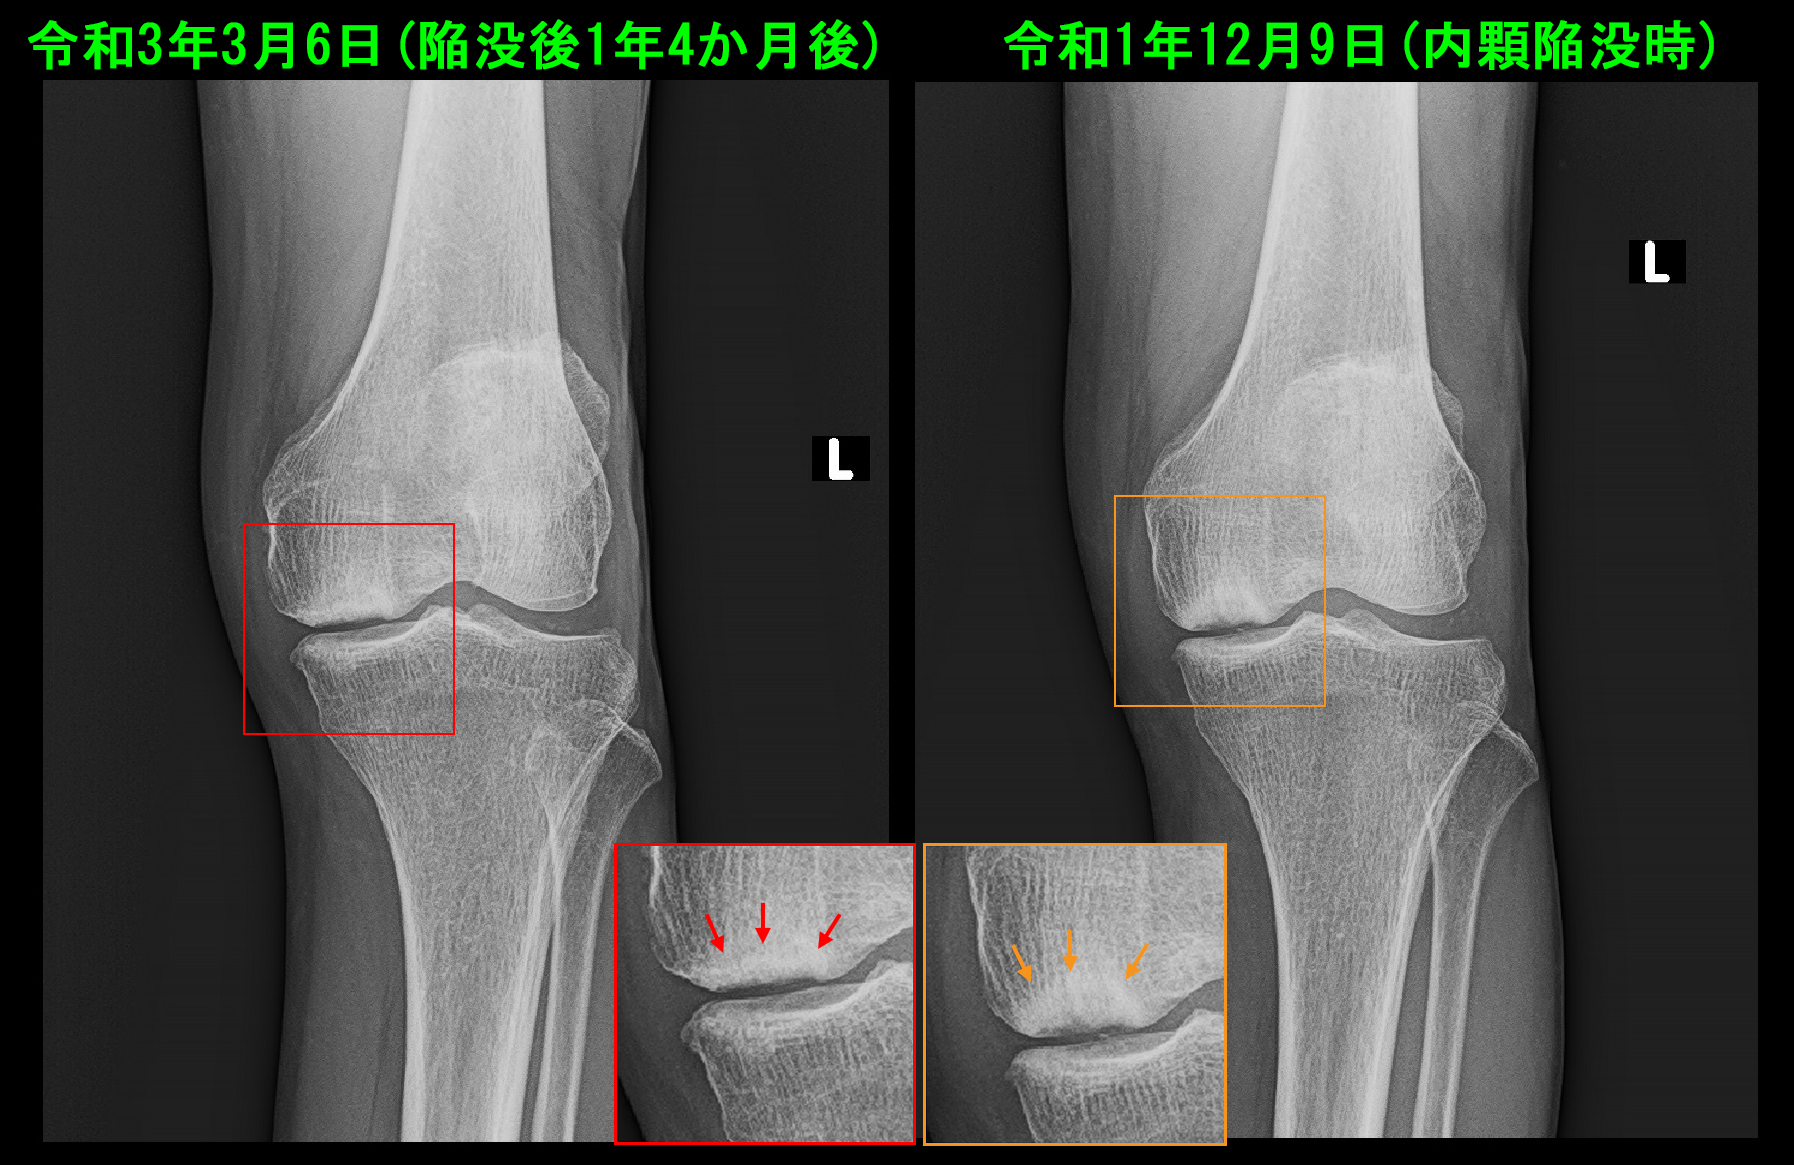

80才 陥凹時Xp.jpg

初診時には連続性がみられた(オレンジ矢印)大腿骨の関節面の骨のラインの連続性が絶たれています。(赤矢印)

令和3年3月6日のレントゲン像では関節裂隙は保たれており、陥凹した関節面の骨は再形成されて埋まってきていることが確認可能です。同年5月以降、患者さんの受診は終了しました。